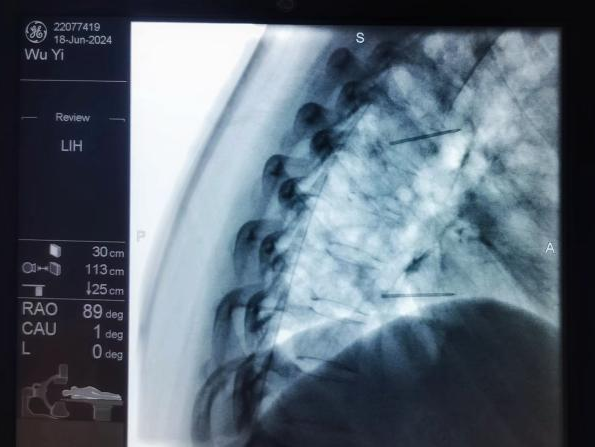

椎間盤射頻消融術(shù)、膠原酶椎間盤化學(xué)消融術(shù):兩種都是治療椎間盤突出癥的微創(chuàng)介入技術(shù)。射頻消融通過高頻電流汽化部分髓核,膠原酶則是通過化學(xué)酶溶解髓核,均能降低椎間盤壓力,從而解除神經(jīng)壓迫。

圖片

椎間盤射頻消融術(shù)、膠原酶椎間盤化學(xué)消融術(shù)